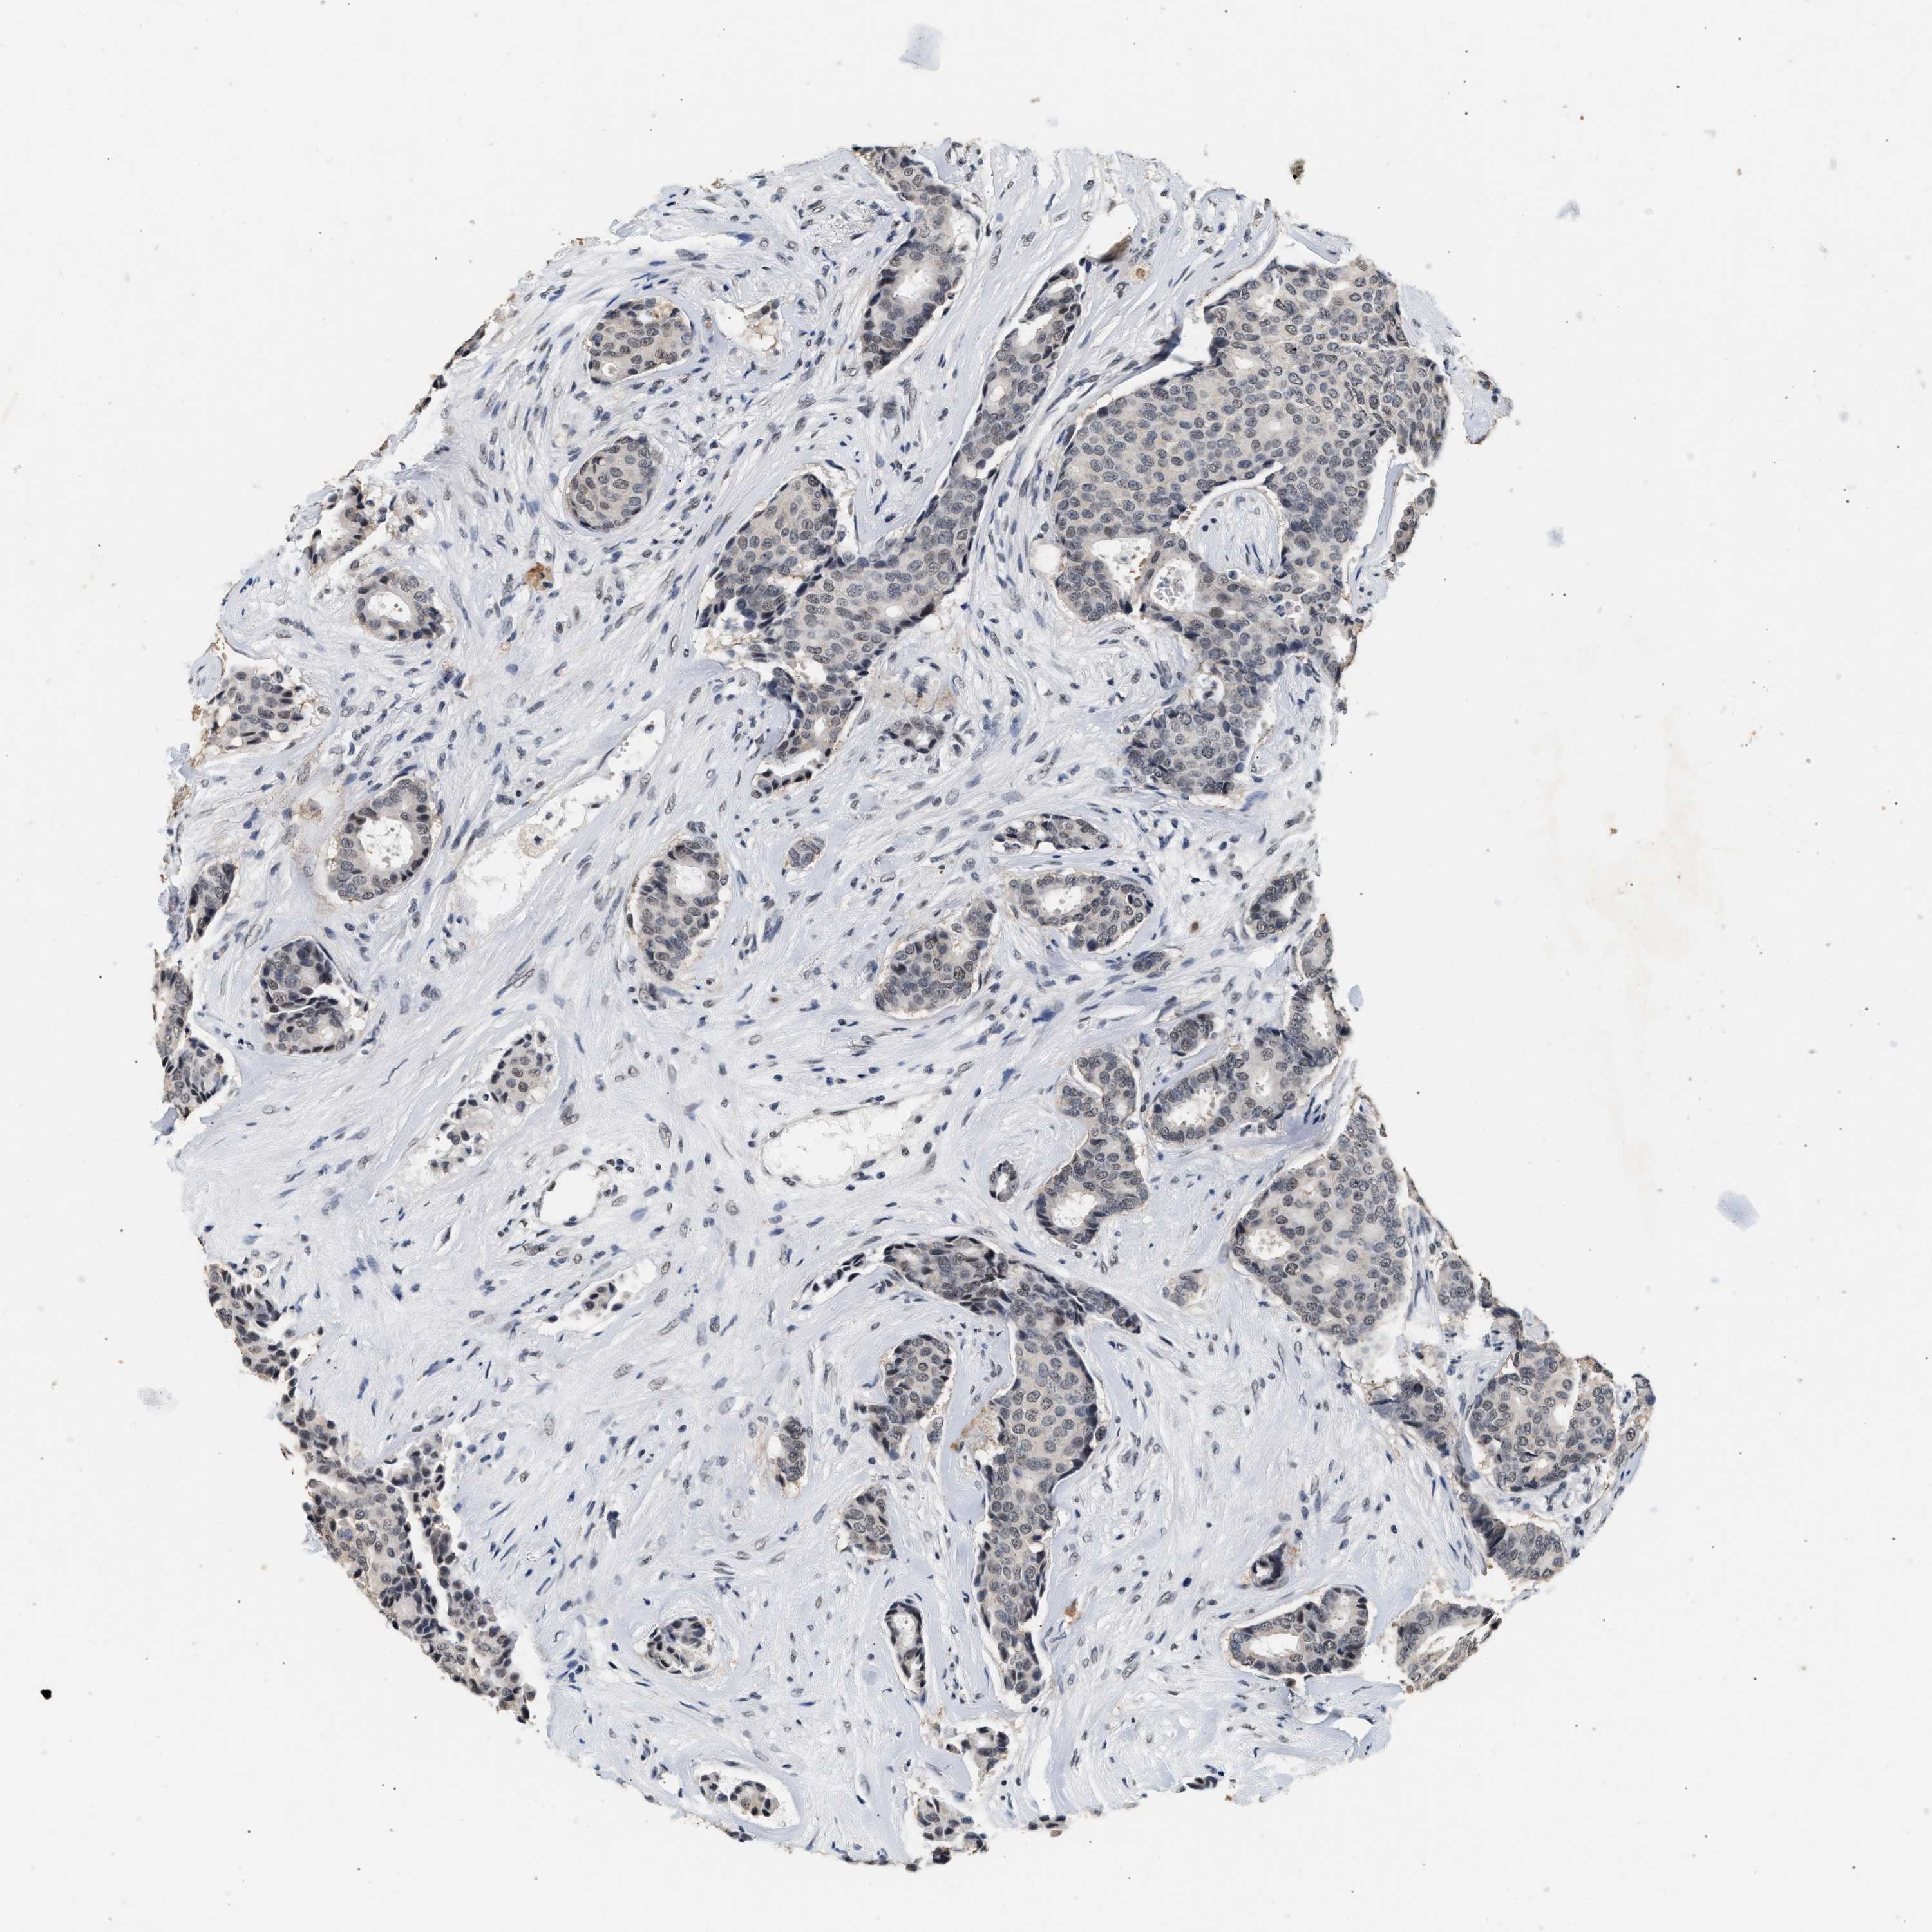

CANCER BREAST CANCER Show tissue menu

BRCA TCGA BRCA VALIDATION PROTEIN EXPRESSION